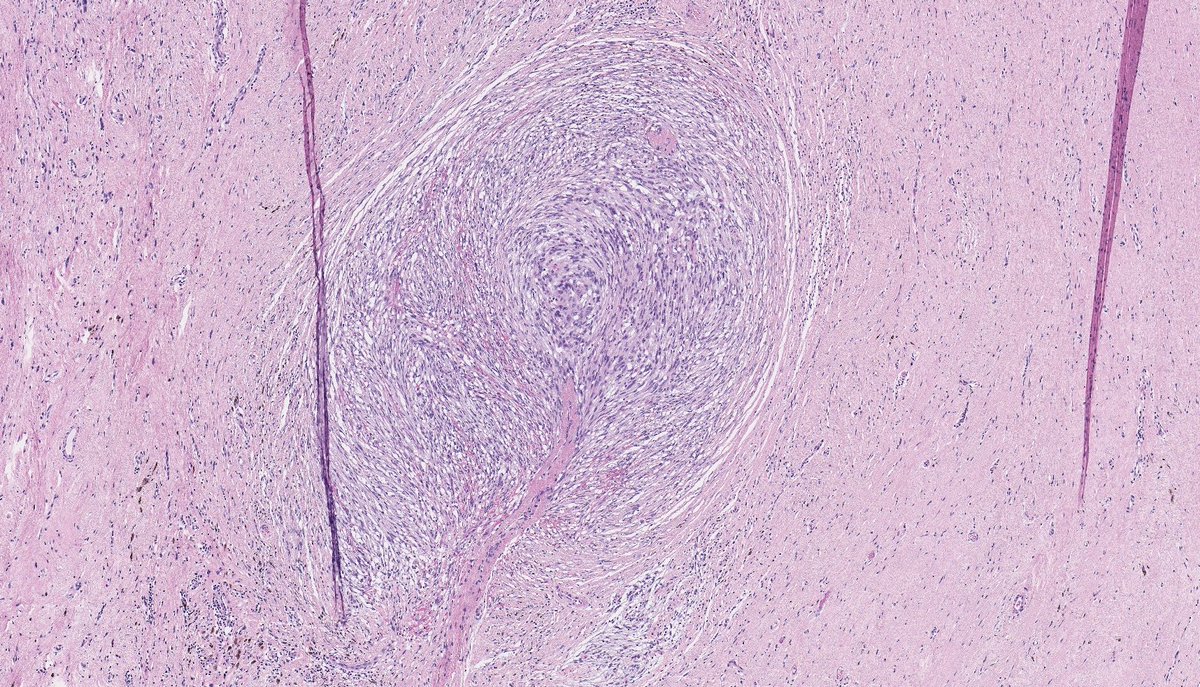

DEDIFFERENTIATED LIPOSARCOMA (with meningothelial-like whorls and metaplastic bone formation). (FISH: + MDM2 amplification.) PMID: 9839165, 21317707.